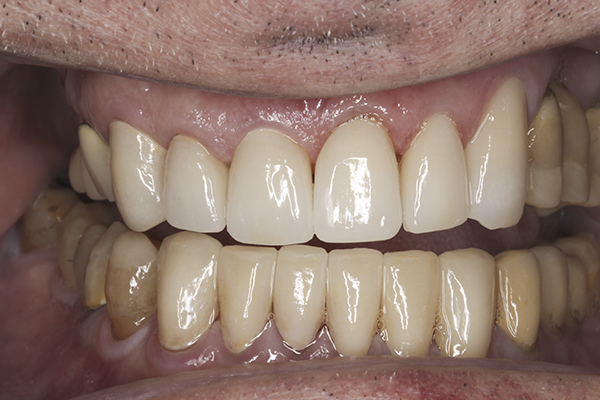

(36.) Postoperative anterior, closed view. Note the position of the upper and lower canines to provide canine guidance.

Figure 36